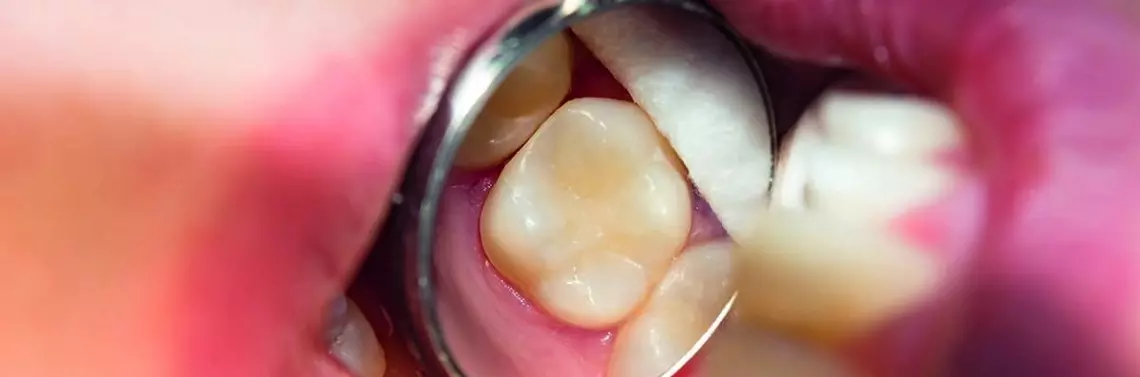

Pacjentka zgłosiła się z prośbą o wymianę wypełnienia amalgamatowego. Wypełnienie wolne było od defektów, a motywacją pacjentki do zmiany była rozpętana burza medialna o związanych z posiadaniem takich wypełnień skutkach ubocznych. Wykorzystując ostatnie chwile przed koniecznością instalowania separatorów do amalgamatu, podjęto zabieg (zdj. 1).

Stan początkowy: widoczne pęknięte, ale zachowujące szczelność wypełnienie amalgamatowe klasy pierwszej wg Blacka w zębie 37. Podczas preparacji usunięto wypełnienie amalgamatowe, zachowując warstwę materiału podkładowego – decyzję podjęto w związku z brakiem oznak próchnicy. Zastosowano system łączący One Coat 7 Universal i poddano go polimeryzacji. Następnie warstwowo aplikowano materiał Brilliant EverGlow w kolorze A3/D3. Po polimeryzacji wypełnienie dostosowano do zwarcia i wypolerowano (zdj. 2).